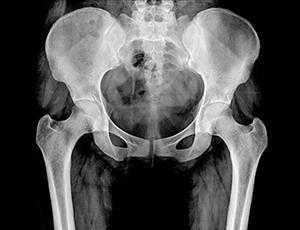

Технические параметры рентгенографии таза и тазобедренных суставов

Максимальную визуальную информацию дает рентген тазобедренного сустава в двух проекциях: в прямой проекции (или фронтальной), получаемой фокусировкой рентгеновской трубки перпендикулярно плоскости тела — спереди или сзади, и аксиальной (поперечной или горизонтальной плоскости), фиксирующей элементы сустава сверху вниз — вдоль бедренной кости. Также снимок может делаться при боковой проекции, то есть пациент должен лечь на бок, согнув ногу в коленном и тазобедренном суставах.

Каждая рентгенограмма дает важную информацию, необходимую для точной диагностики заболеваний тазобедренного сустава . Как правило, переднезадний профиль предоставляют информацию о форме вертлужной впадины, тогда как другие боковые изображения предоставляют информацию о проксимальных отделах бедра, включая головку бедра.

На рентгенограммах переднезаднего бедра может быть получена следующая информация:

- длина ноги,

- угол шейки,

- покрытие вертлужной впадины: угол наклона латерального центрального края (СЕ) и индекс выдавливания головки бедра,

- глубина вертлужной впадины,

- наклон вертлужной впадины,

- версия вертлужной впадины,

- сферичность головы и

- ширина суставного пространства.

На боковых рентгенограммах тазобедренных суставов оценивается форма и смещение сочленения головки бедра и бедреной кости, а также смещение угла альфа.

Рентген тазобедренных суставов проводится в двух проекциях, которые помогают расширить визуализируемую анатомическую область и точно определить объем поражения:

- Передняя проекция. Пациента укладывают на спину, ноги разводят максимально в стороны, что позволяет раскрыть сустав и увеличить площадь диагностики.

- Боковая проекция. Пациент ложится на бок, вытягивает ноги вперёд.

Рентген костей таза и тазобедренных суставов может проводиться в трех проекциях: переднезадней (ПЗ), заднепередней (ЗП) и латеральной (боковой). На снимке спереди видны тазовые кости от верхней части гребня подвздошной кости до проксимального отдела диафиза бедренной кости, лобковая и седалищная кости, тазобедренный сустав, запирательные отверстия, большие вертелы проксимального отдела бедра в профиль.

На снимке сбоку визуализируется крестец, копчик, пояснично-крестцовый переход, наложенные друг на друга бедренные кости и верхняя часть бедра.